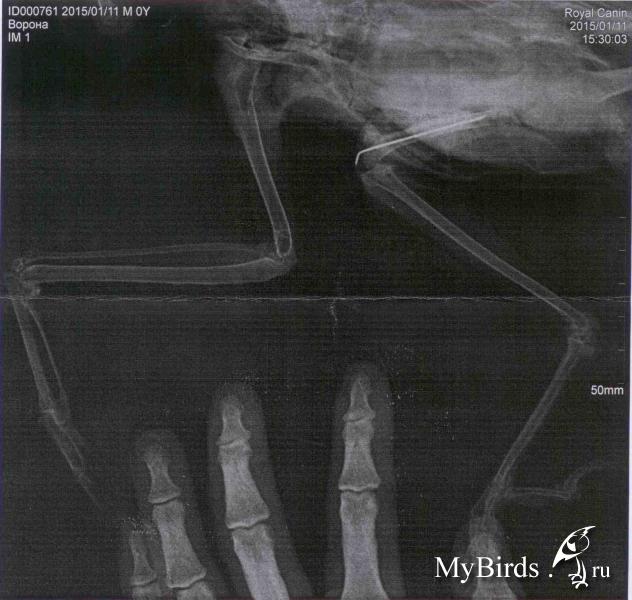

Lala87 Опубликовано 15 января, 2015 Автор #62 Опубликовано 15 января, 2015 На днях истек срок в 21 день, поехали в клинику, сделали рентген (прикрепляю, хотя врядли там можно что-то разобрать). Сказали, что срастается, но пока не до конца, нужно еще 2 недели походить со спицей.